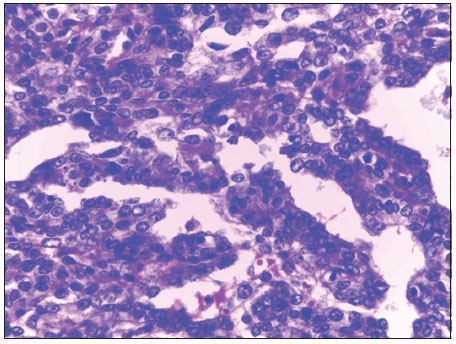

| Figure 3 Malignant adnexal skin tumor, High-power photomicrograph showing basaloid epithelial cells with frequent mitotic activity (arrows). (H and E, ×400)